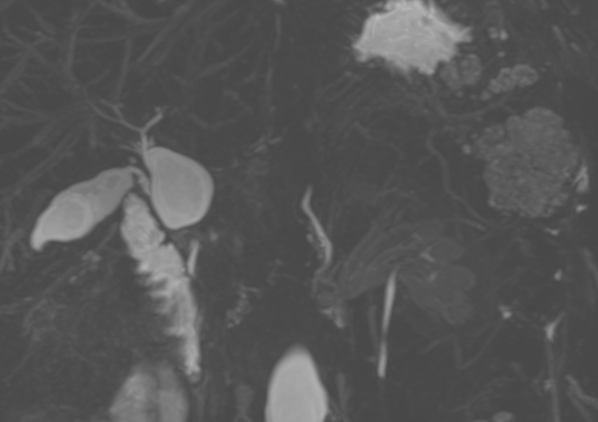

If you're having trouble choosing between an extracellular or hepatobiliary contrast agent for liver MRI, why not both? Read about the indications, protocol, and utility of dual-contrast liver MRI, now available in @RadioGraphics at pubs.rsna.org/doi/10.1148/rg…